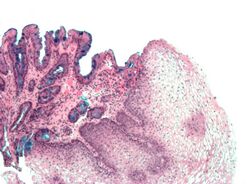

Micrograph of

Barrett's esophagus (left of image) and normal stratified squamous epithelium (right of image). Alcian blue stain.